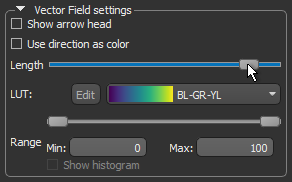

- Use the Length slider to adjust the length of the vectors.

- Choose another look-up table (LUT) in the LUT drop-down menu.

NOTE The Jet LUT is often a good color scheme choice. In this LUT, vectors corresponding to the highest surface anisotropy are colored red, while those corresponding to the lowest, or are isotropic, are colored blue.

- Threshold the vector field-based map to show only high or low anisotropy areas with the Range slider, as shown below.